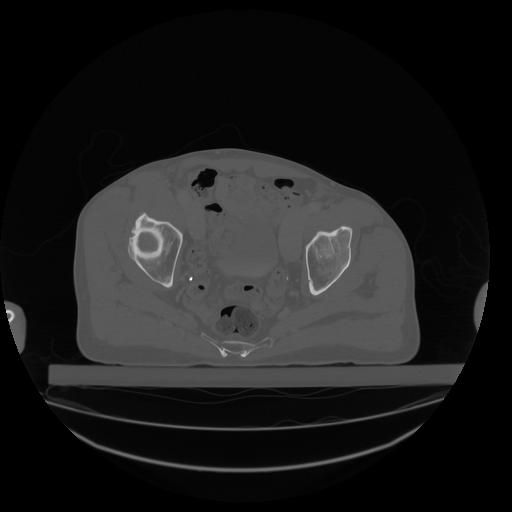

34 CUERPO,CE,Vol,1.0,CUERPO,,